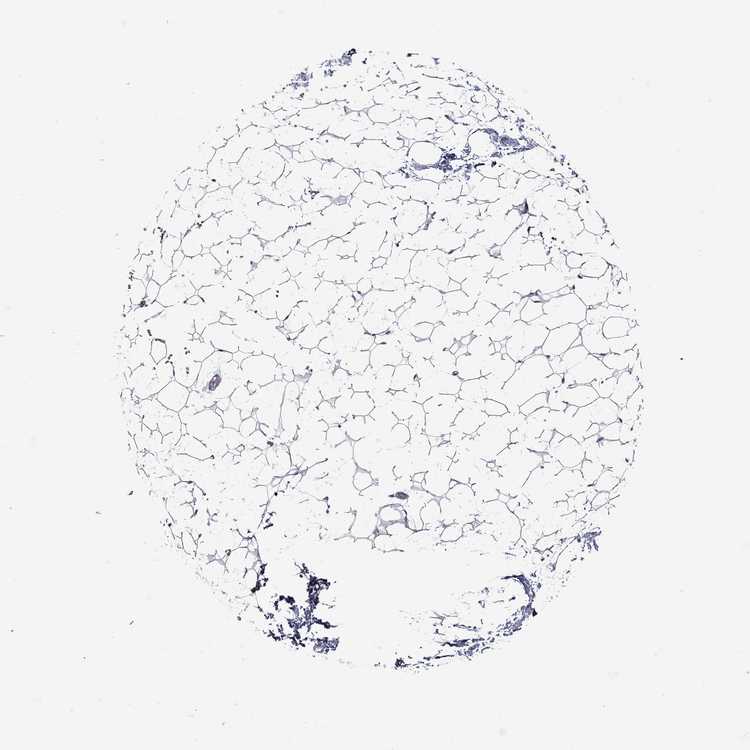

TISSUE PRIMARY DATA SOFT TISSUE Show tissue menu

SOFT TISSUE - Expression summary

SOFT TISSUE 1 - Antibody stainingi

Antibody staining in the annotated cell types in the current human tissue is reported as not detected, low, medium, or high, based on conventional immunohistochemistry profiling in selected tissues. This score is based on the combination of the staining intensity and fraction of stained cells.

Each image is clickable and will lead to virtual microscopy that enables deeper exploration of all samples and also displays staining intensity scores, fraction scores and subcellular localization as well as patient and tissue information for each sample.

Antibody HPA046700Antibody HPA076024

Fibroblasts Not detectedNot detected

Peripheral nerve -Not detected